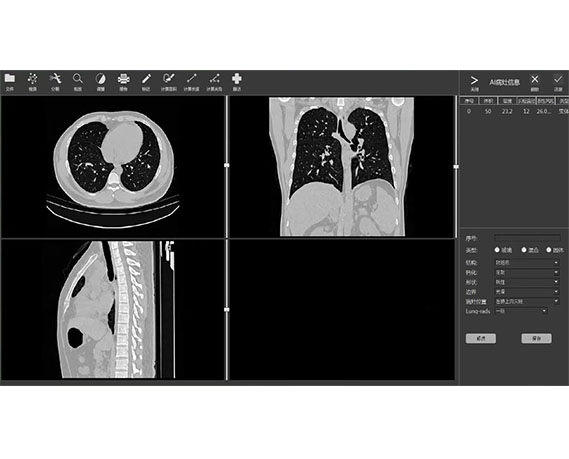

View X-Ray CT & MRI Scans Fast and Easily

Very fast and easy to use

Traditional multi-planar slicing

Multi-planar slicing.

Oblique slicing.